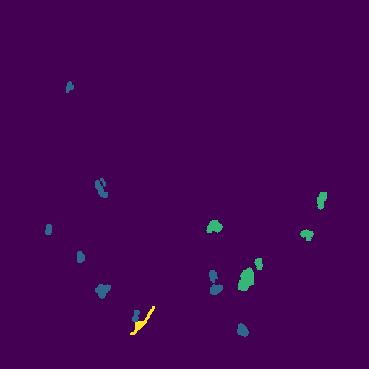

The novel coronavirus disease 2019 (COVID-19) has been spreading rapidly around the world and caused significant impact on the public health and economy. However, there is still lack of studies on effectively quantifying the lung infection caused by COVID-19. As a basic but challenging task of the diagnostic framework, segmentation plays a crucial role in accurate quantification of COVID-19 infection measured by computed tomography (CT) images. To this end, we proposed a novel deep learning algorithm for automated segmentation of multiple COVID-19 infection regions. Specifically, we use the Aggregated Residual Transformations to learn a robust and expressive feature representation and apply the soft attention mechanism to improve the capability of the model to distinguish a variety of symptoms of the COVID-19. With a public CT image dataset, we validate the efficacy of the proposed algorithm in comparison with other competing methods. Experimental results demonstrate the outstanding performance of our algorithm for automated segmentation of COVID-19 Chest CT images. Our study provides a promising deep leaning-based segmentation tool to lay a foundation to quantitative diagnosis of COVID-19 lung infection in CT images.